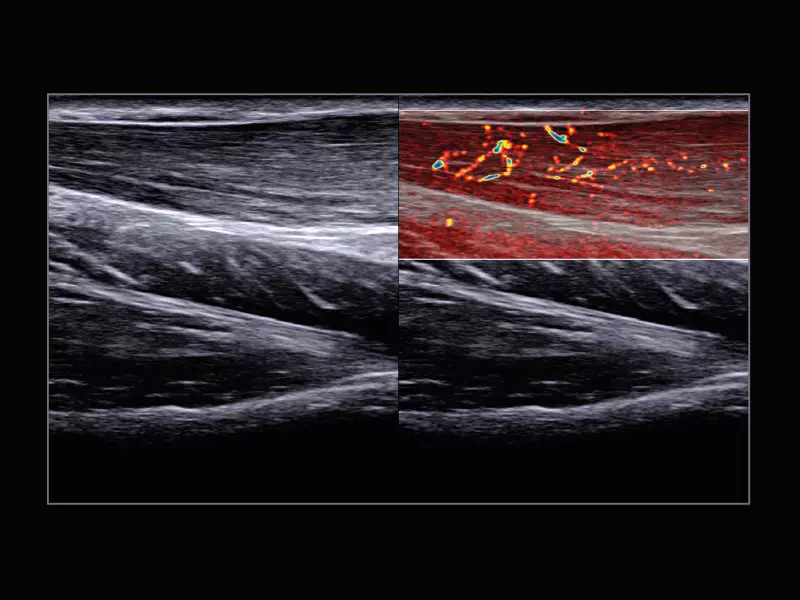

MyLab™C25 - X-FLOW 2

MyLab™C25 - X-FLOW 2